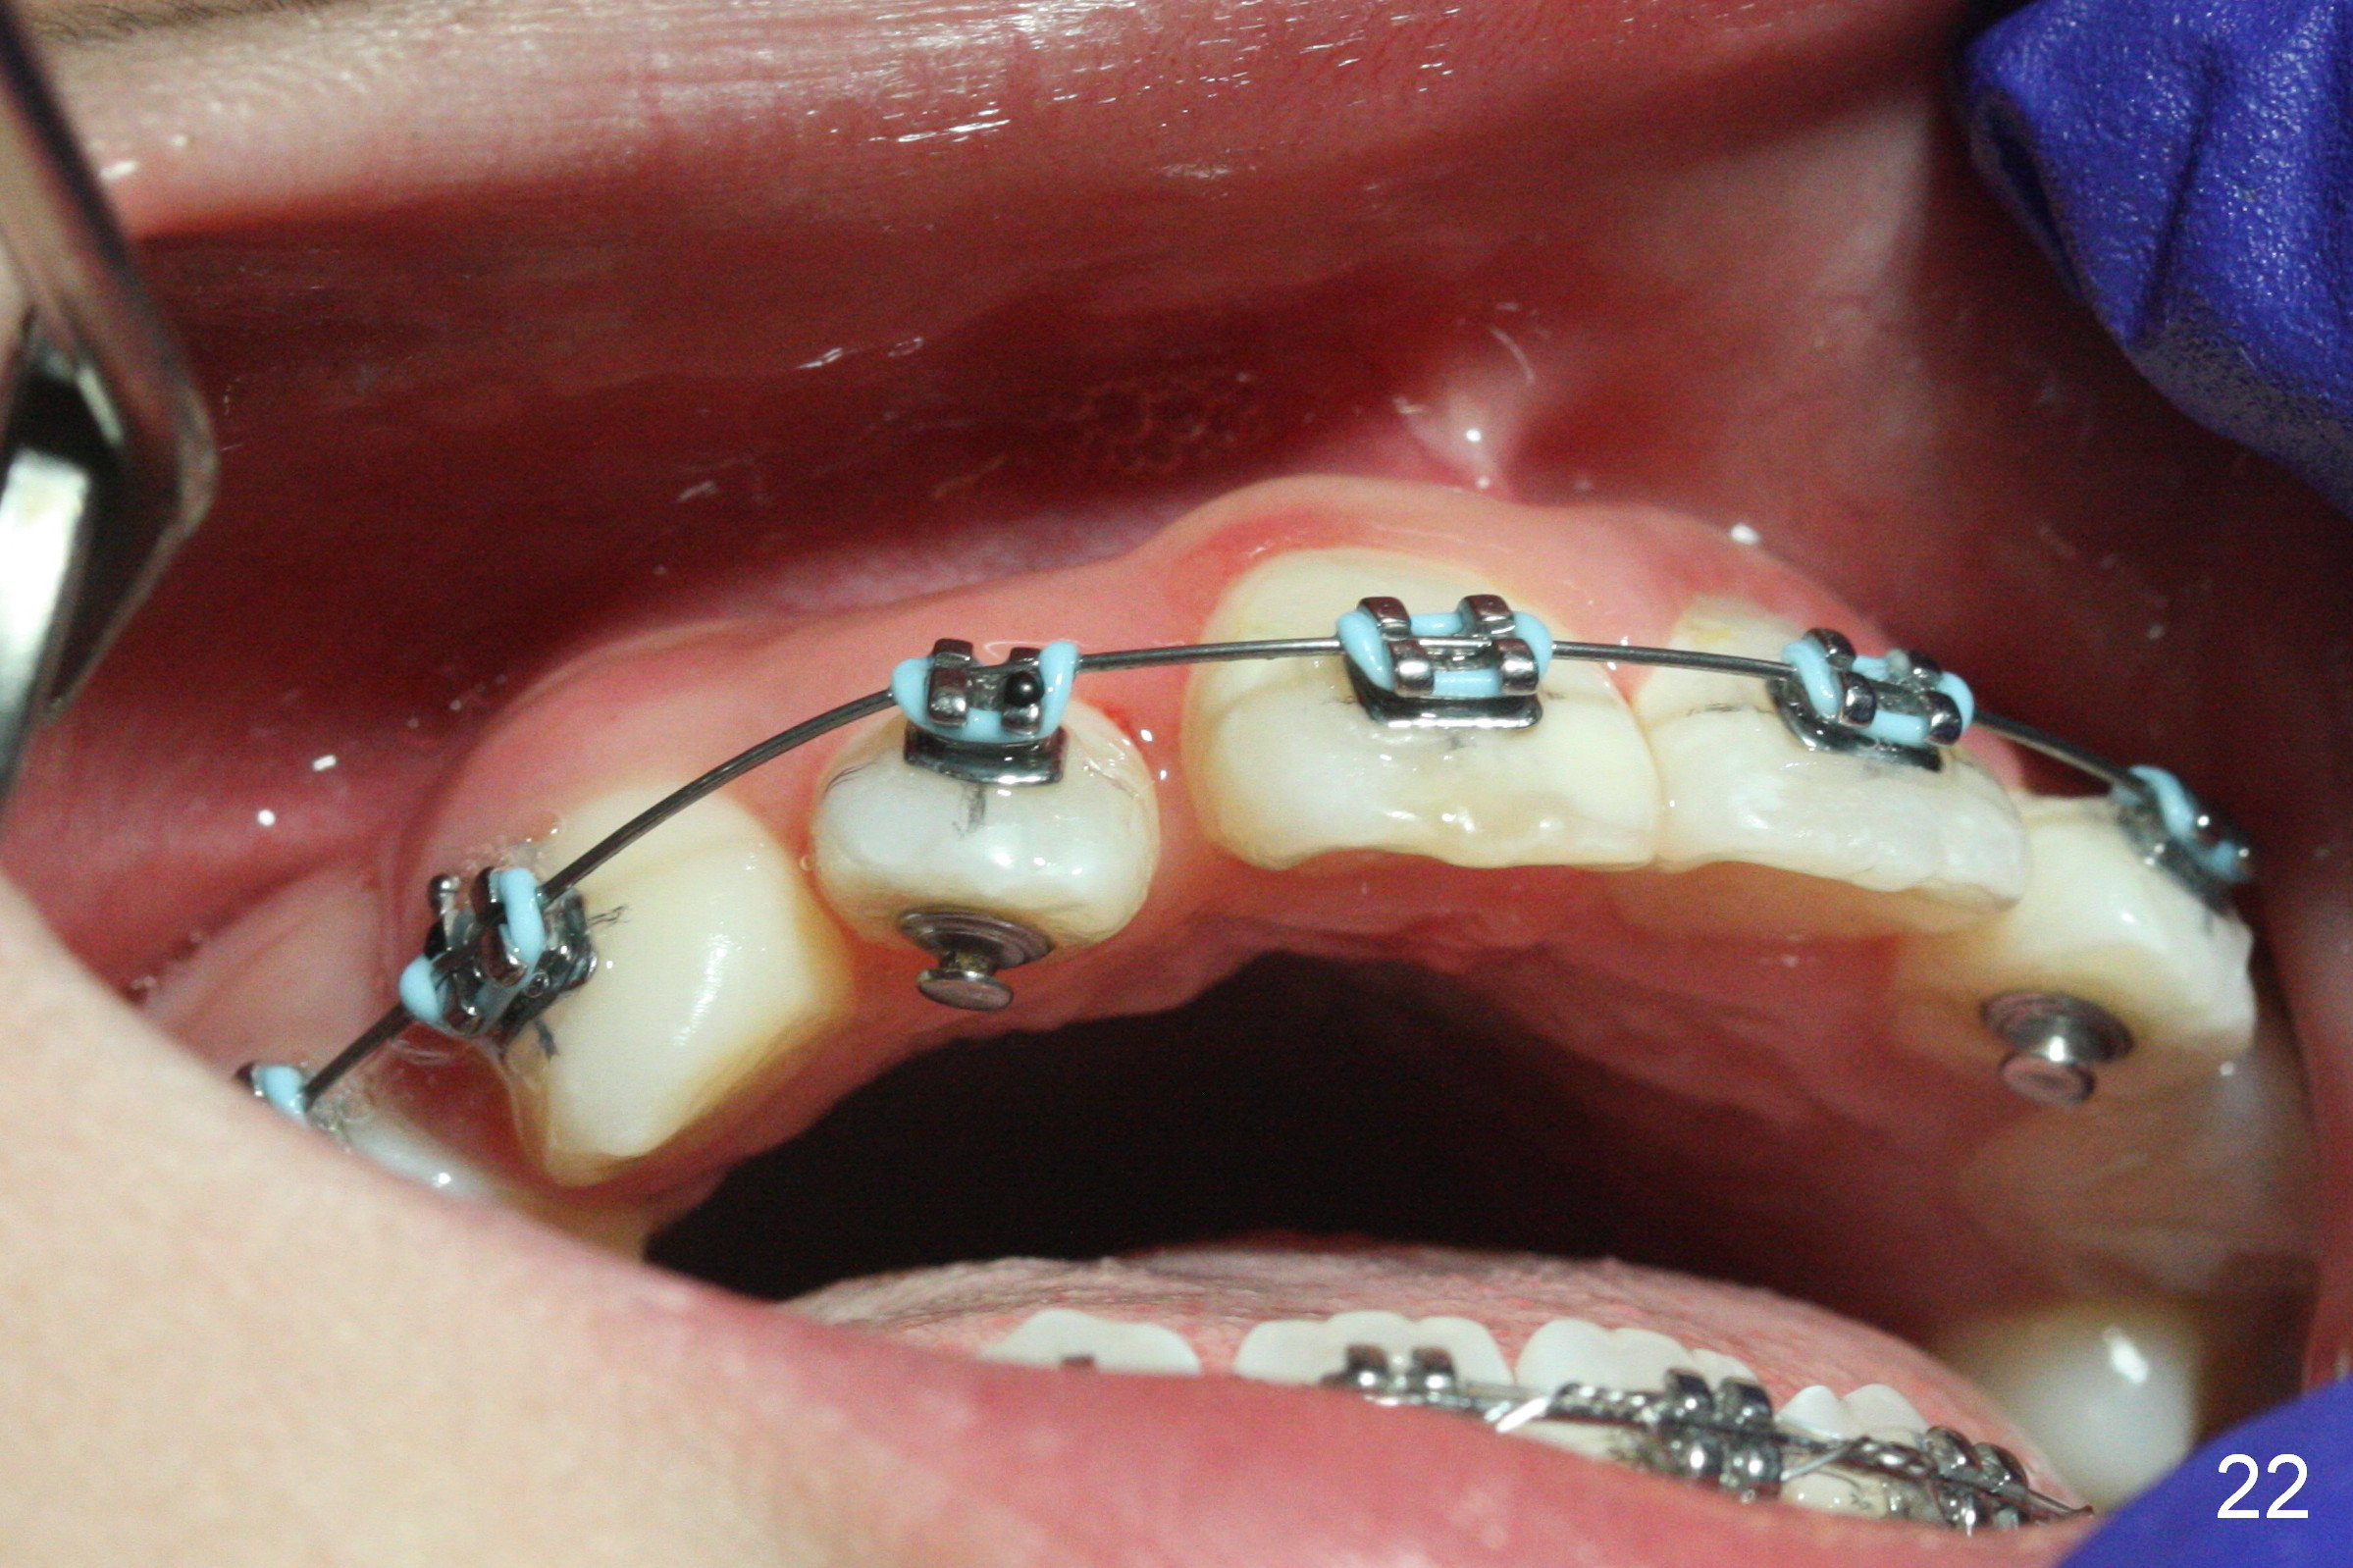

One month of open coil spring between UR1 and 3 (18 ss), power chain is placed with 3 loops between UR2 and 3 and 5 loops between UR 1 and 2 (Fig.21, sling shot). One month later, bracket is placed at UR2 (upside down) and 16 niti wire is engaged (Fig.22). While L3-3 is laced, power chain is placed between LR 3 and 5 with intention to mesialize the latter (Fig.23 arrow) so that there will be enough space to de-rotate LR7 (Fig.24). Can we at the same time place a separator between LR 6 and 7 to mesialize LR6 and distalize LR7?